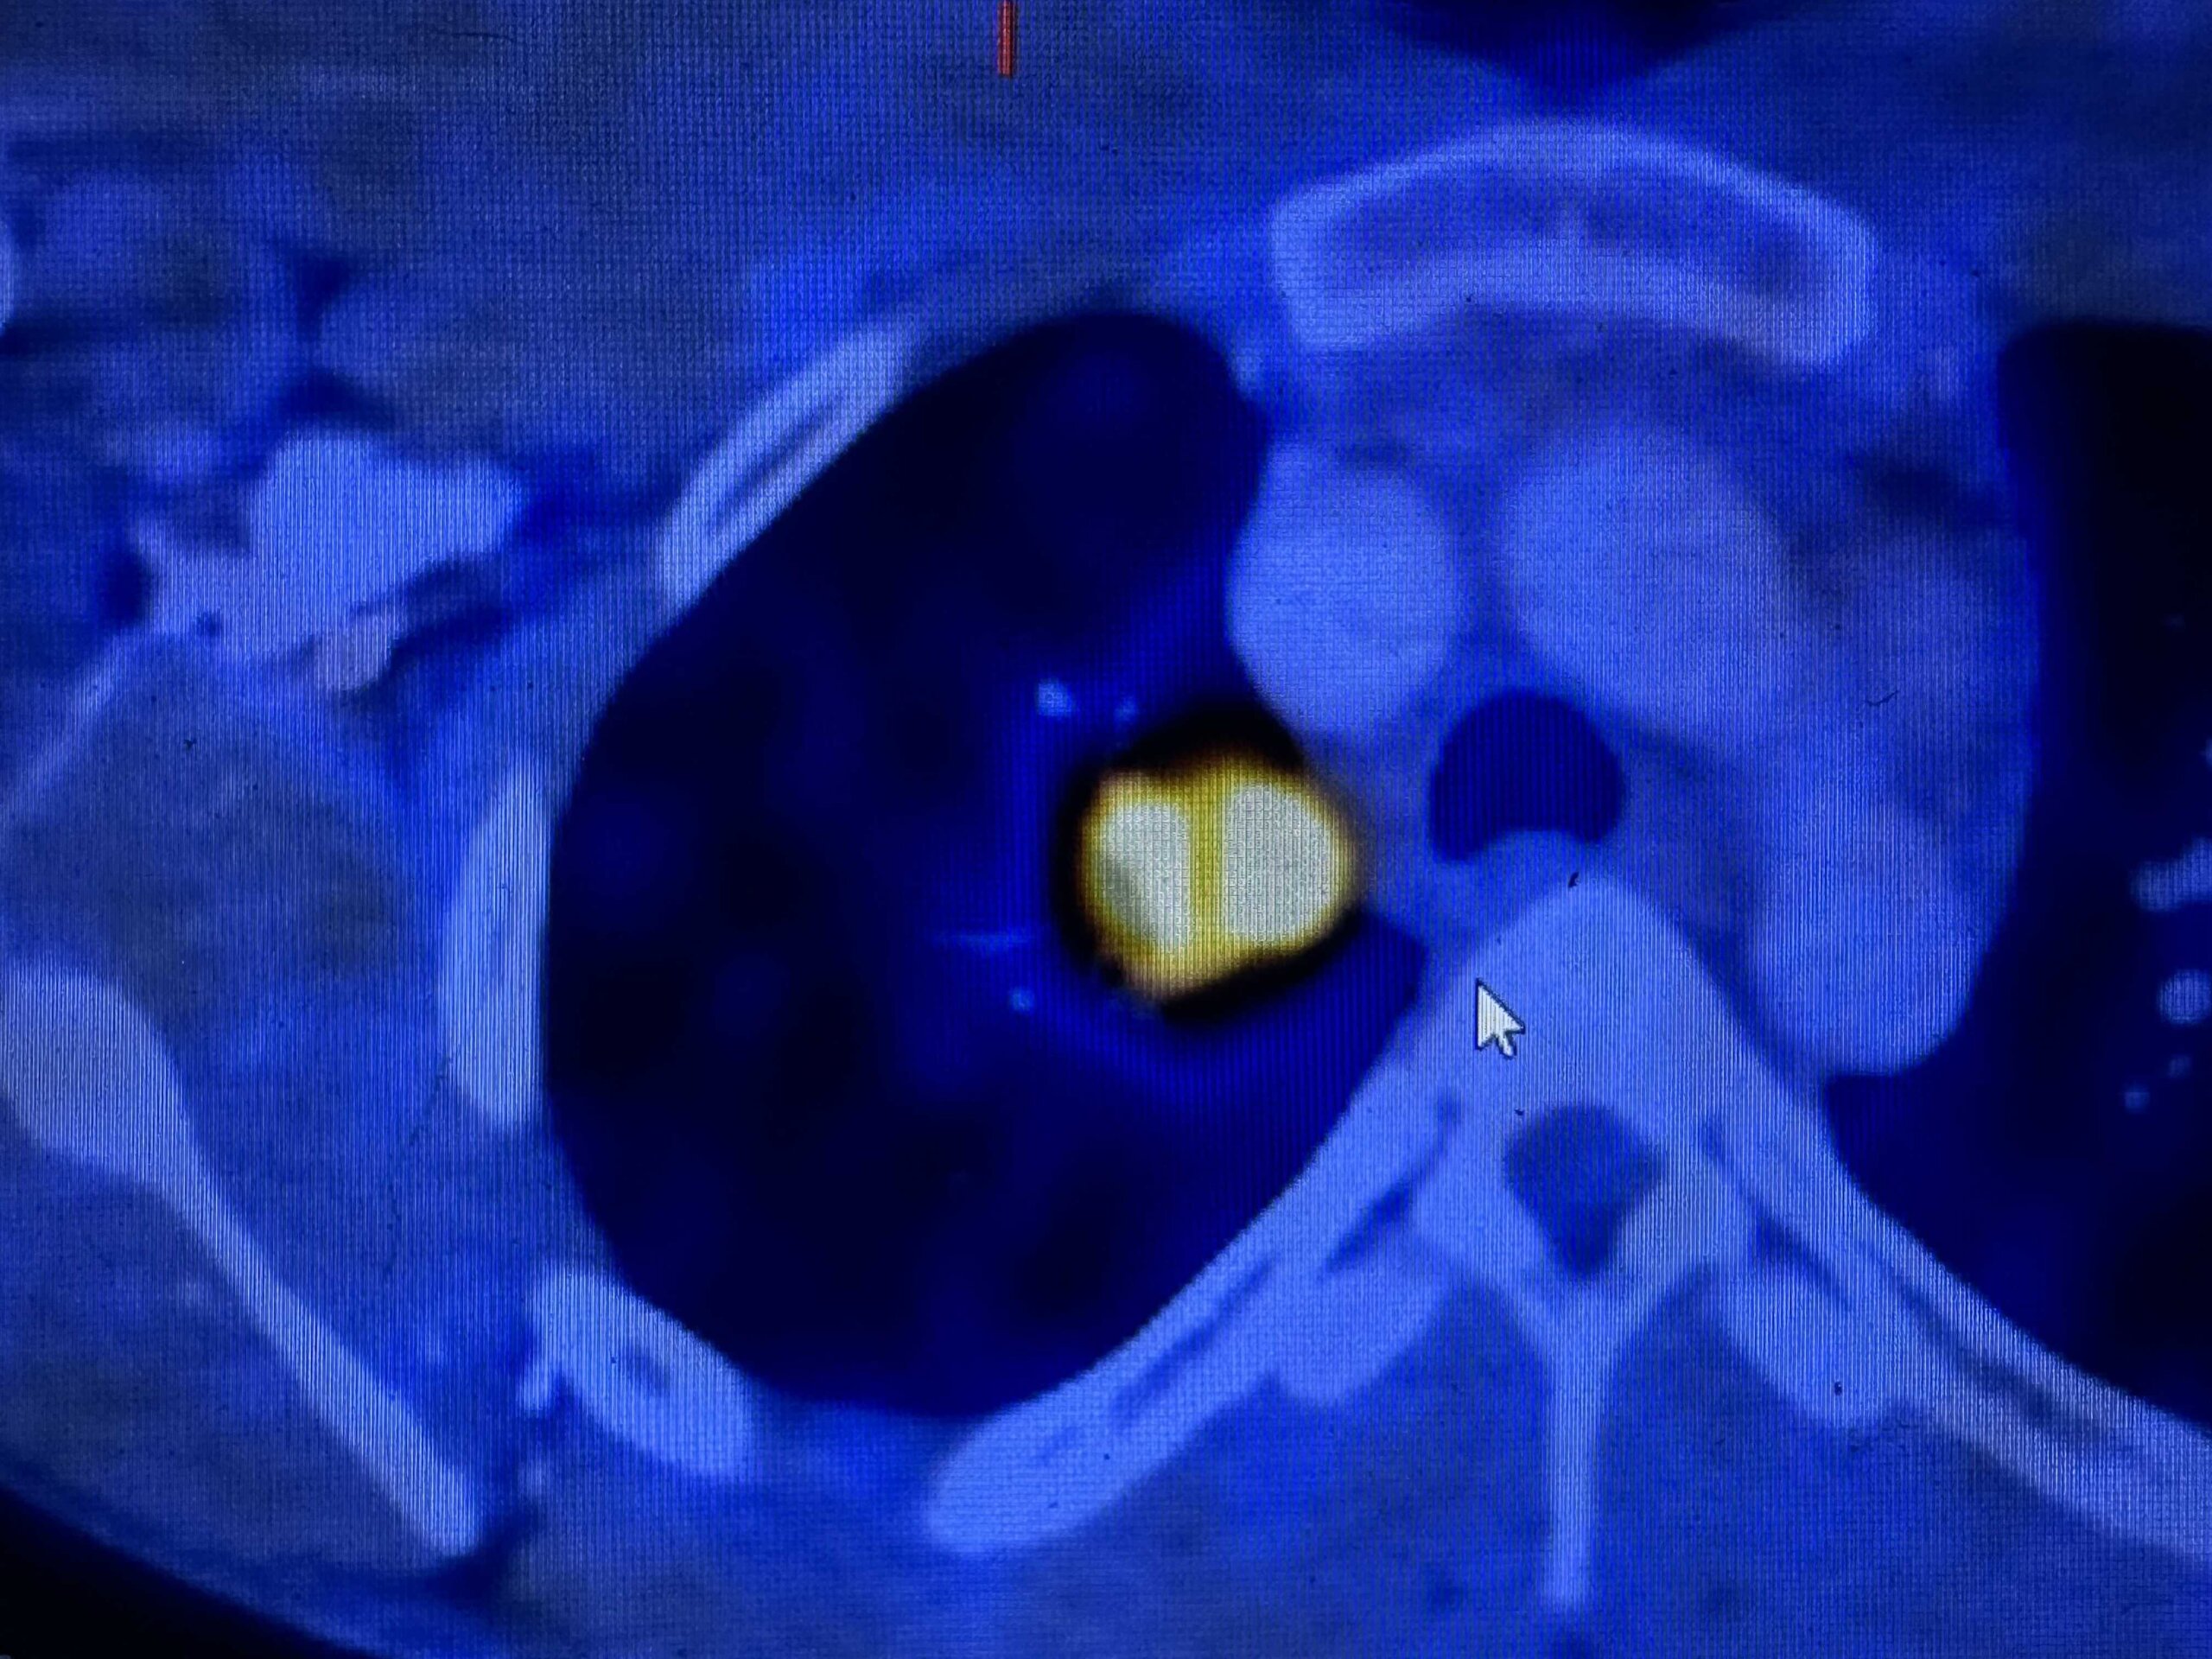

הביולוגיה של HNSCC

הבסיס הנדרש להבנת סרטן ראש-צוואר. מתחילים מהיסוד, עולה בהדרגה